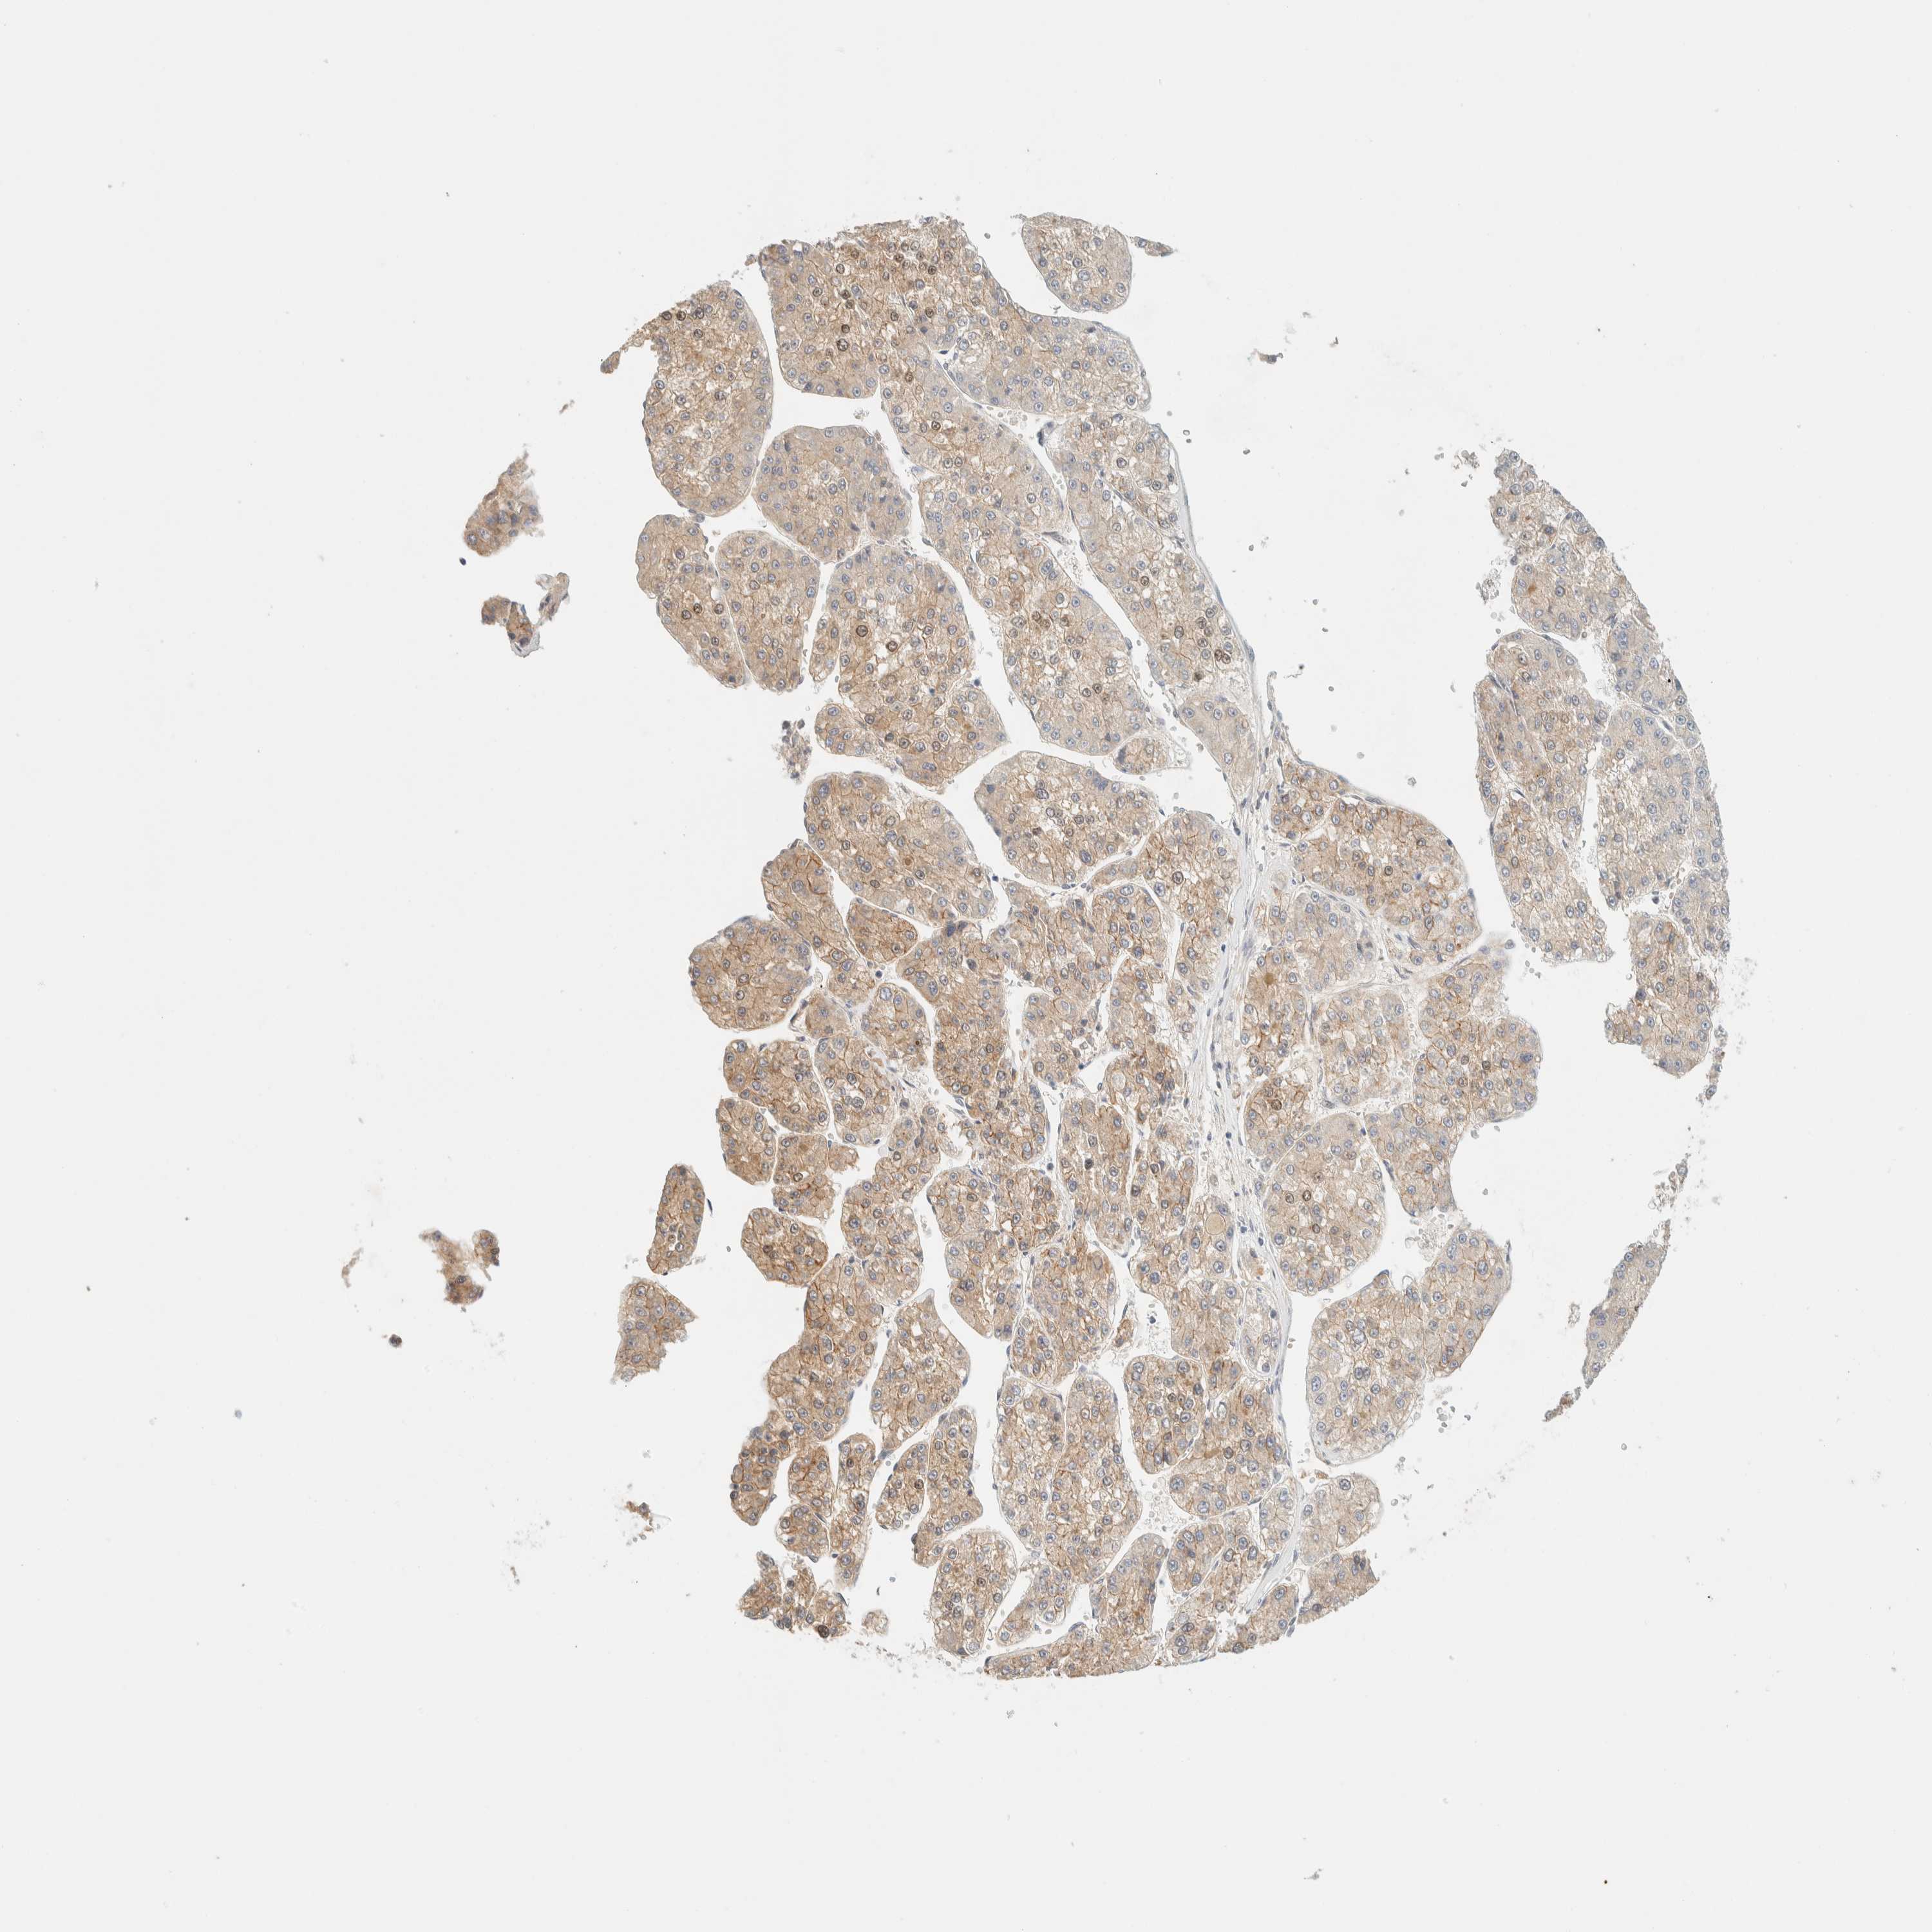

LIVER CANCER - Protein expressioni

A mouse-over function shows sample information and annotation data. Click on an image to view it in a full screen mode. Samples can be filtered based on level of antibody staining by selecting one or several of the following categories: high, medium, low and not detected. The assay and annotation is described here.

Note that samples used for immunohistochemistry by the Human Protein Atlas do not correspond to samples in the TCGA dataset.

Antibody stainingi

Antibody staining in the annotated cell types in the current human tissue is reported as not detected, low, medium, or high, based on conventional immunohistochemistry profiling in selected tissues. This score is based on the combination of the staining intensity and fraction of stained cells.

Each image is clickable and will lead to virtual microscopy that enables deeper exploration of all samples and also displays staining intensity scores, fraction scores and subcellular localization as well as patient and tissue information for each sample.

Antibody HPA001869

Antibody HPA023882

Staining

High

Medium

Low

Not detected

Intensity

Strong

Moderate

Weak

Negative

Quantity

>75%

75%-25%

<25%

None

Location

Nuclear

Cytoplasmic/membranous

Cytoplasmic/membranous,nuclear

Cholangiocarcinoma

Carcinoma, Hepatocellular, NOS